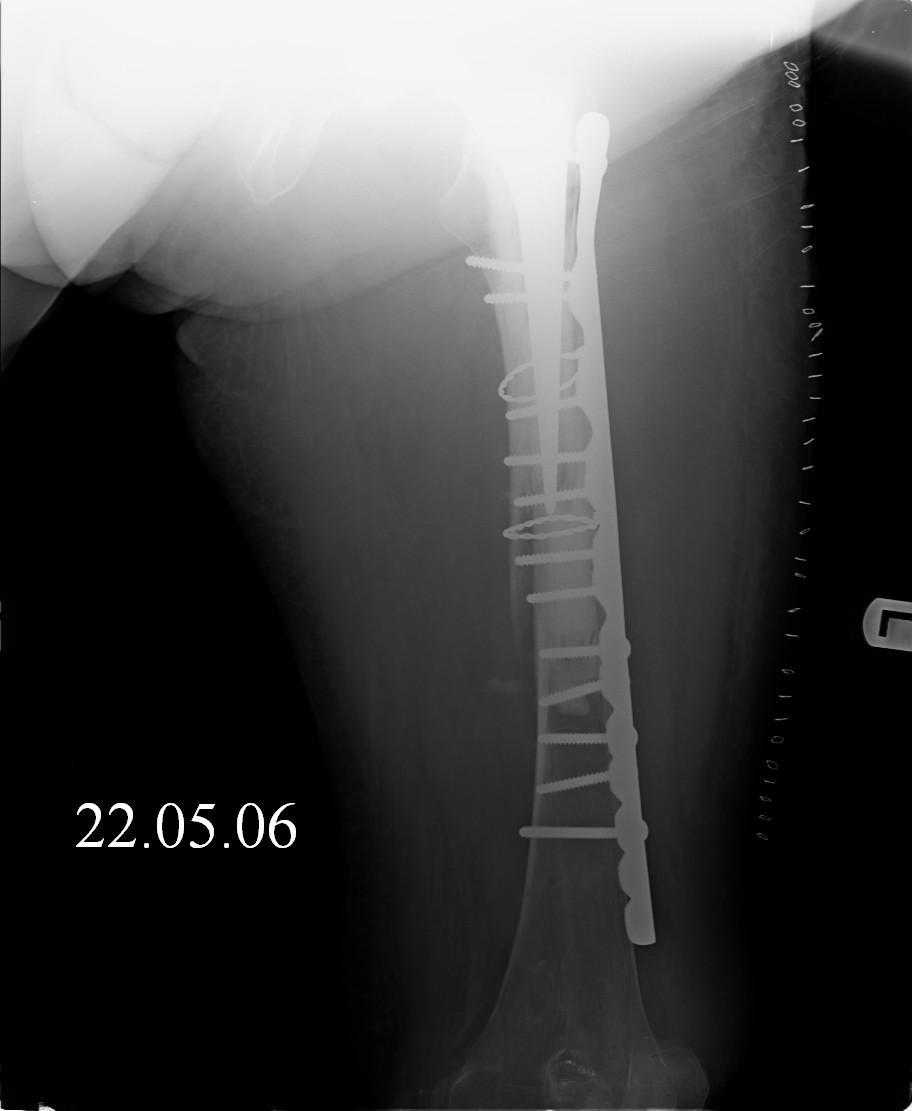

Спасибо за обсуждение. После нескольких дней тракции аппаратом сделали. Попытка закрытой репозиции не удалась из-за смещения по ширине, мешали фрагменты цемента. После их удаления репозиция получилась. Еще убрали немного цемента с ножки по латерльной стороне, чтобы обнажить 40-50 мм ее дистальной части, для плотной посадки гвоздя. Дальнейшее введение гвоздя было несложным. Протез показался нам стабильным в проксимальной части как латерально, так и медиально. Картинки в приложении.

THX for the discussion. After few days of traction by ex-fix the surgery was performed. An attempt of closed nailing was unsuccesful because of fragment translation, which was blocked by cement fragments. After removal of broken cement pieces reduction was reached "automagically". Also some cement from lateral part was removed by

chisel to expose distal 40-50 mm of the stem to allow tight fit of the nail. Further fixation by the nail was pretty easy and straightforward. Images attached. The stem looked stable in its proximal part both laterally and medially. Comments/critics are welcome.